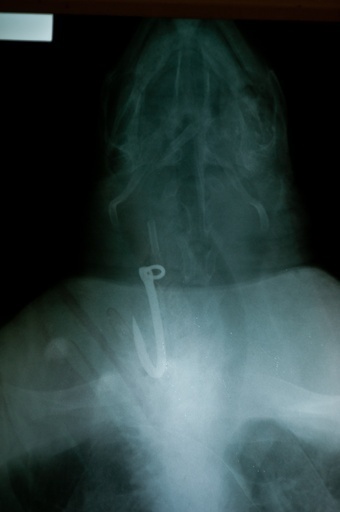

食道に釣り針、ウミガメ2匹を治療 エルサルバドル